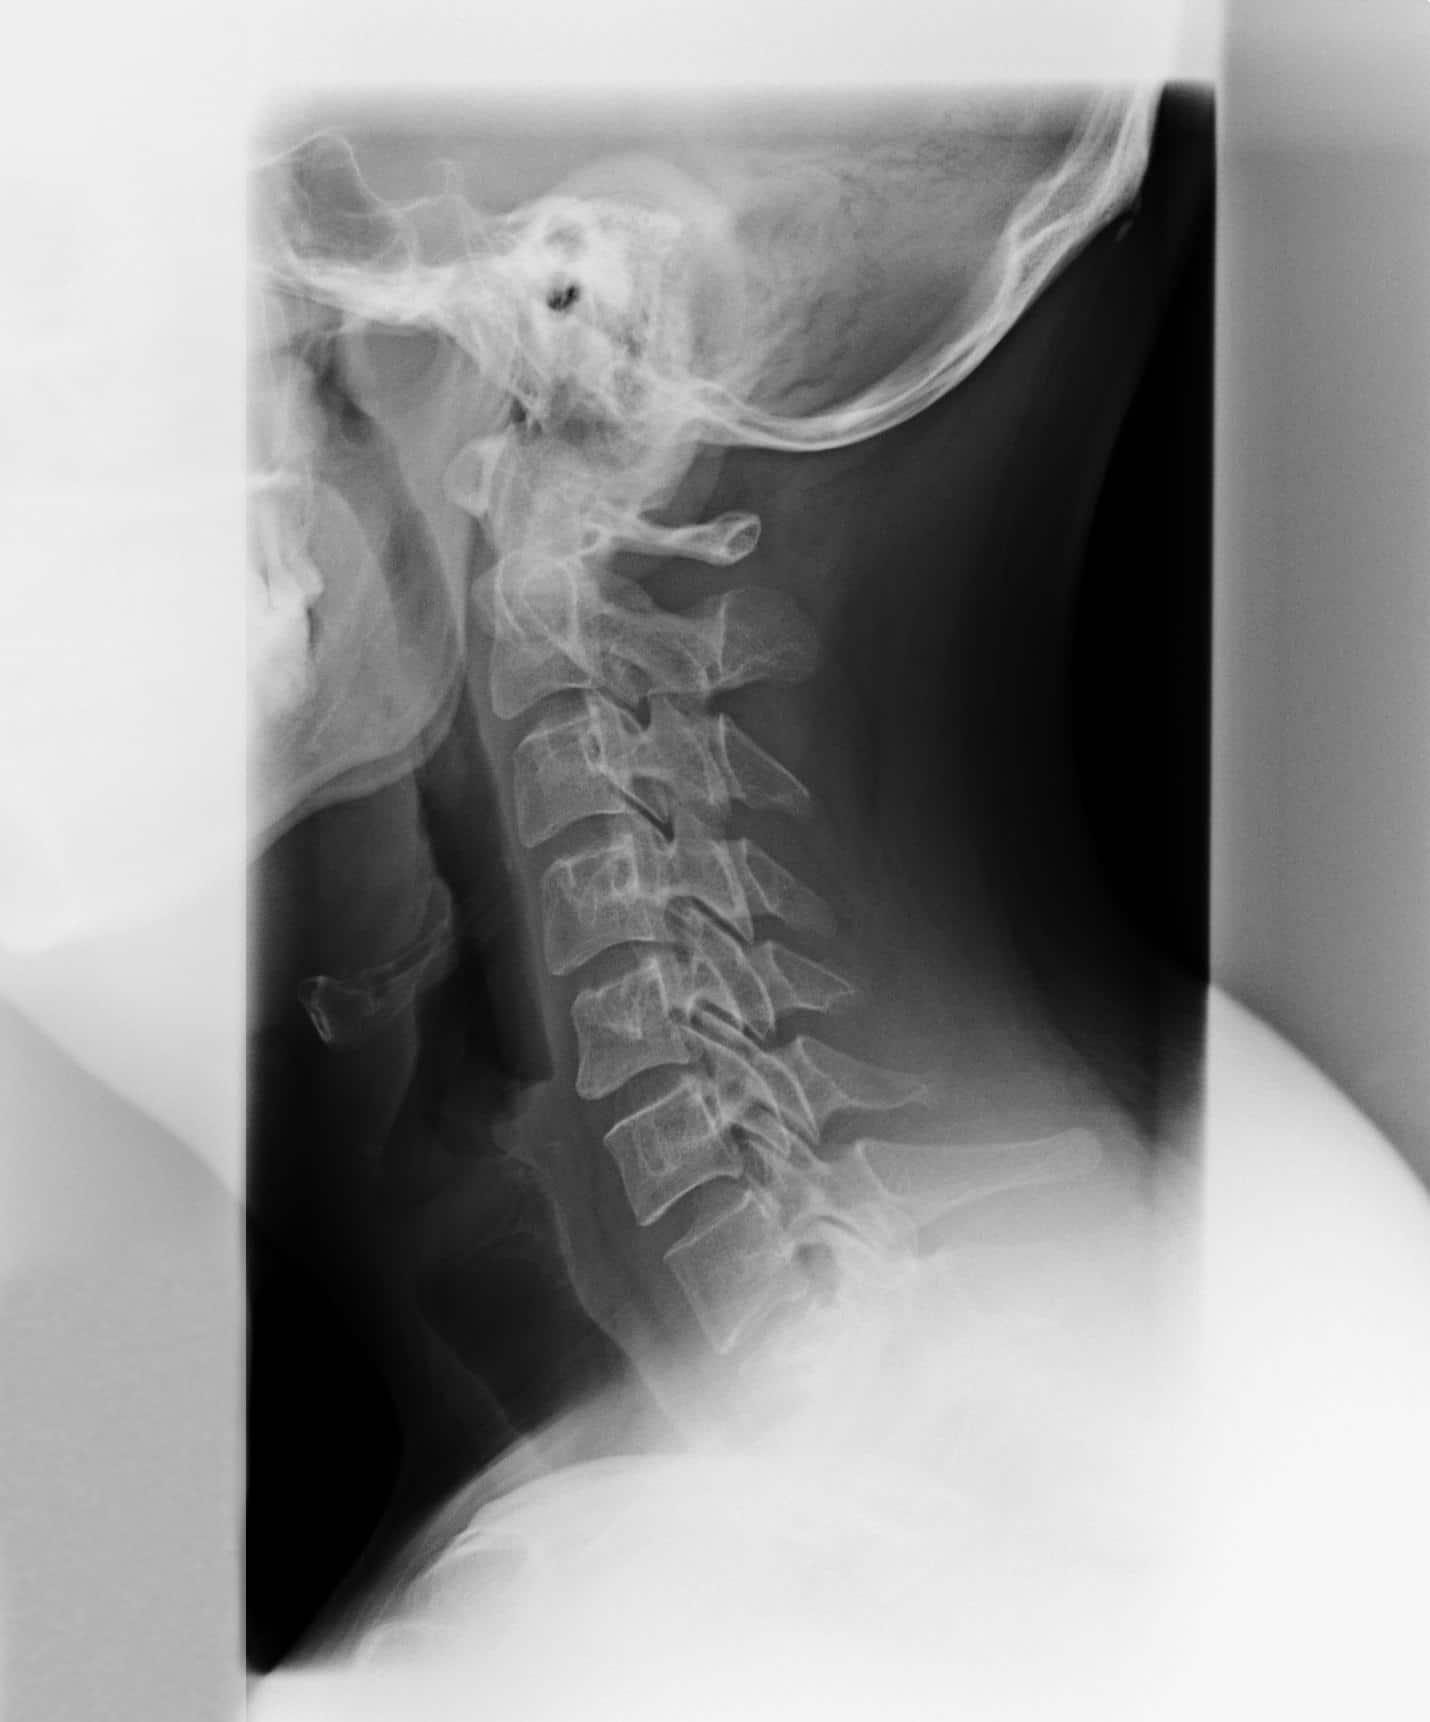

Phase IV Degeneration

In the final stage of subluxation degeneration. At this point, you experience a marked decrease in the quality of life, and longevity is lessened. Neurological and bone damage previously suffered are permanent and the vertebrae are fused. Range of motion may be severely limited and a number of other health issues may present.

However, with proper chiropractic care, the patient can sometimes relieve pain and improve overall nervous function enough that they can still enjoy living life. This is true even at phase IV. If you may be experiencing symptoms of subluxation degeneration in the Marietta area, contact Intrinsic Chiropractic to schedule an appointment today.